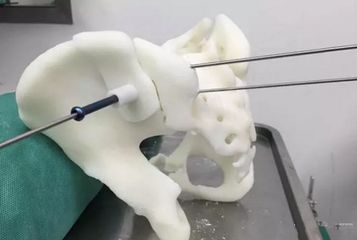

- 打印导板引导导航下的根尖定位

- 各个牙位种植体的颊舌向,近远中图: 数字化种植导板设计和制造需要